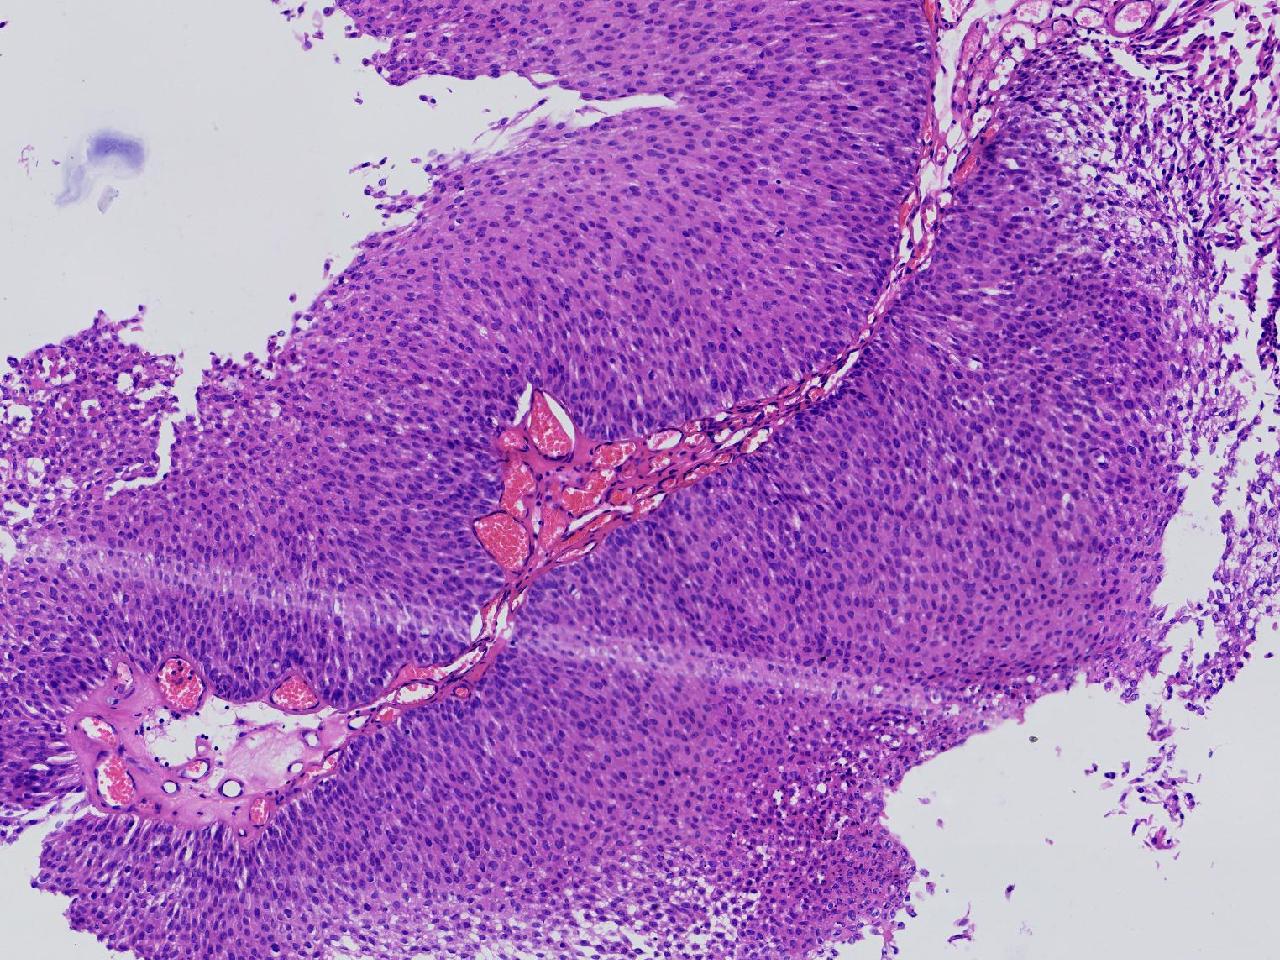

男,79岁,膀胱肿物。

膀胱肿物

灰白色不整形软组织多块,2X1X1厘米。

考虑:乳头状尿路上皮癌

考虑低级别,非浸润。

乳头状尿路上皮癌,低级别。

这几张图片上没有看到明确的浸润。